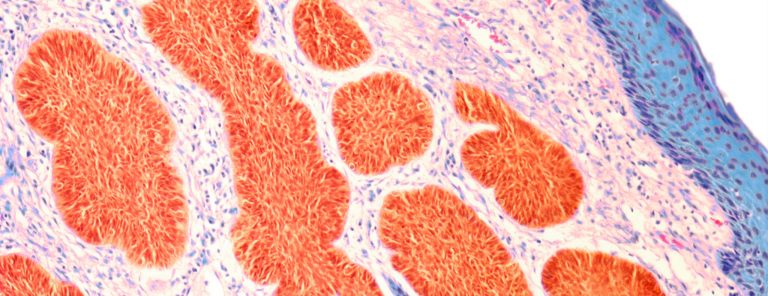

تمتدّ فترة الحمل إلى 40 أسبوعاً، أي ما يقارب تسعة أشهر، وفي كُل أسبوع تحدث مجموعة من التغيرات على الجنين وعلى الأم أيضاً، فيتغيّر طول ووزن الجنين من أسبوع لآخر، وتنمو الأعضاء المختلفة بالتدريج؛ ففي الأسبوع العاشر من الحمل، تكون كُلّ الأعضاء الحيوية كالرئتين والكبد والدماغ والأمعاء تكوّنت بشكل كامل، وتقوم بوظيفتها بفاعلية، وتبدأ تغيّرات جديدة بالحدوث، ومن أبرز التغيرات التي تحصل في هذه المرحلة: نمو الرأس؛ حيثُ إنّه يبدأ بالانفصال عن الصدر، وتنمو العظام أيضاً بوتيرةٍ سريعة، وتبدأ بعض التفاصيل الدقيقة في الظهوركالأذنين، العيون، الأسنان والفم .

تطور الجنين في الأسبوع العاشر

في هذه المرحلة يبلغ طول الجنين 2-3 سنتيمتر، ويصل وزنه إلى 2.5 غرام. تبدأ التفاصيل الدقيقة بالبروز، فتنمو الأذنان ويصبح الطفل قادراً على سماع الأصوات الخارجية وتمييزها والتفاعل معها، لكنّها تنمو في مكان منخفض من الرأس، وفي مراحل متقدّمة ومع استمرار نمو الجنين تتحرّكان لتستقرّا على جانب الرأس.

تبدأ العيون أيضاً بالنمو ولكنها تكون مغطّاةً بالجفون لحمايتها، وتبقى كذلك حتى الأسبوع السابع والعشرين، وتنمو في هذه المرحلة أيضاً براعم الأسنان والتي يبلغ عددها 20 برعماً، وتُشكّل الأسنان اللبنية التي تظهر في الأعوام الأولى من حياته، ومن التفاصيل التي تبدأ بالظهور بشكل أوضح في هذه المرحلة الأصابع؛ حيثُ تبدأ بالانفصال عن بعضها البعض وتصبح أطول وأقوى .